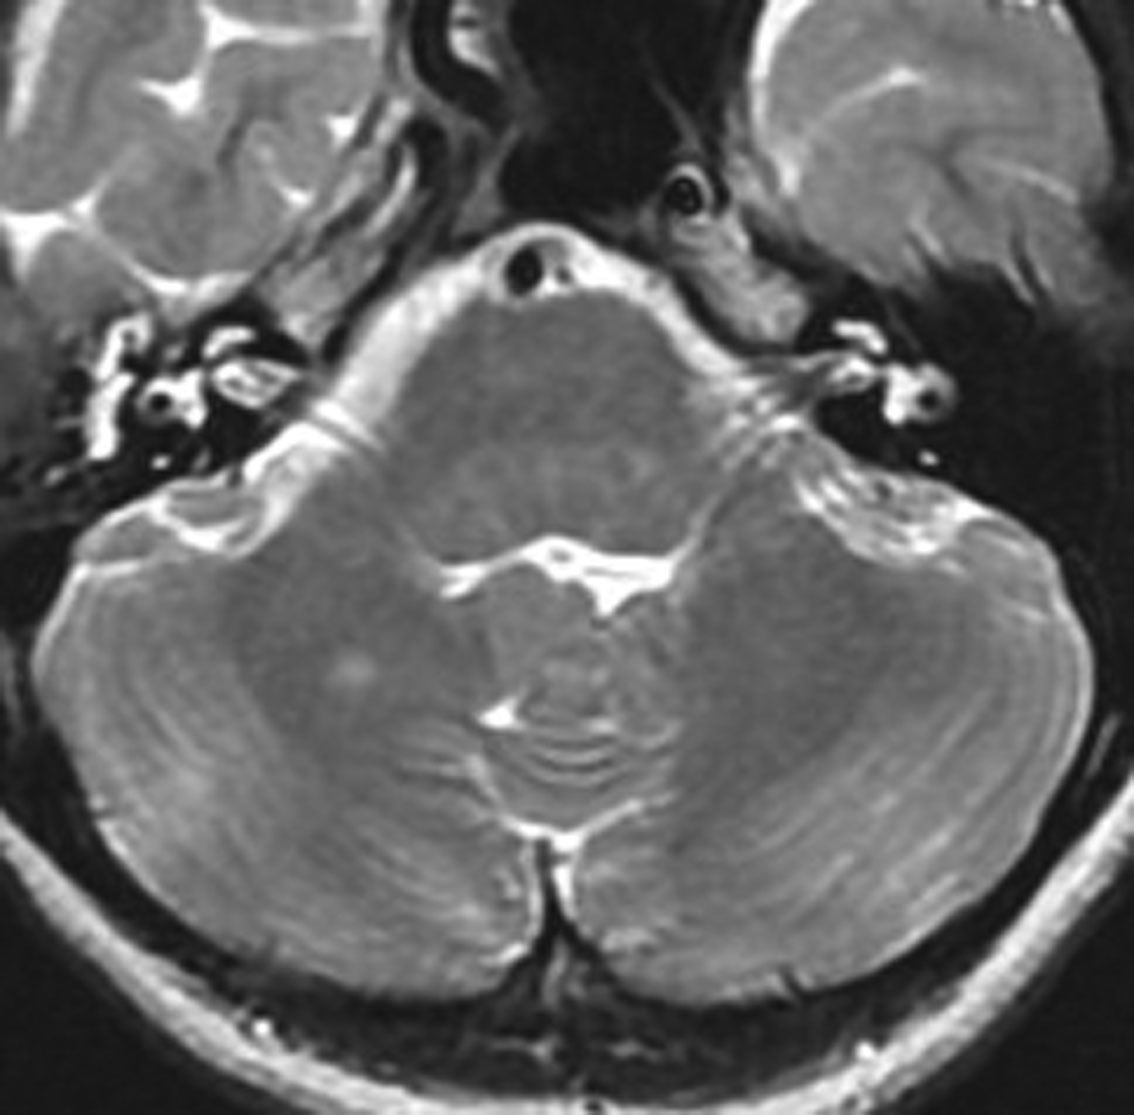

NF-1に見られる典型的なUBOです。白くにじむように見えるところが,両側の大脳基底核から視床に散在しています。脳幹部にも同時に見られることが多いです。もちろん治療の必用はありません。